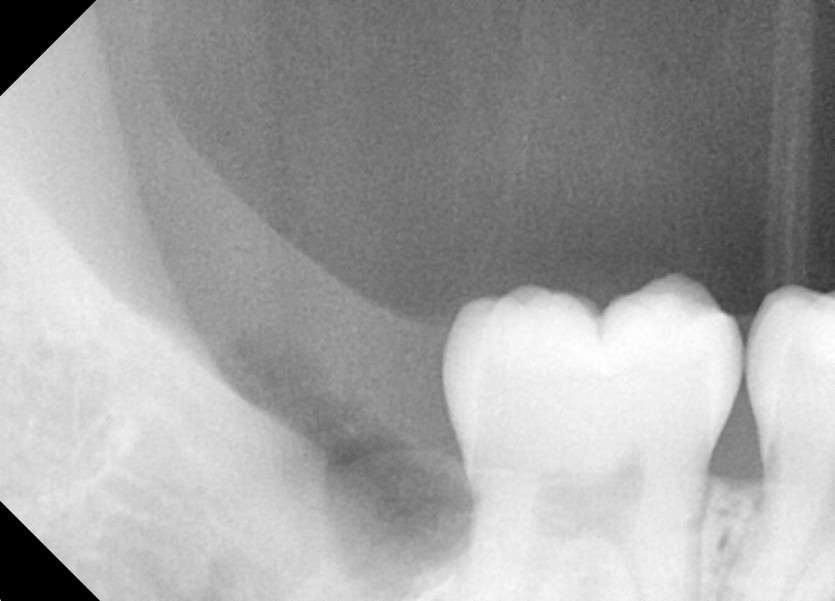

#18,28,38,48 사랑니 발치

구강 외과 전문의가 당일 발치했습니다.